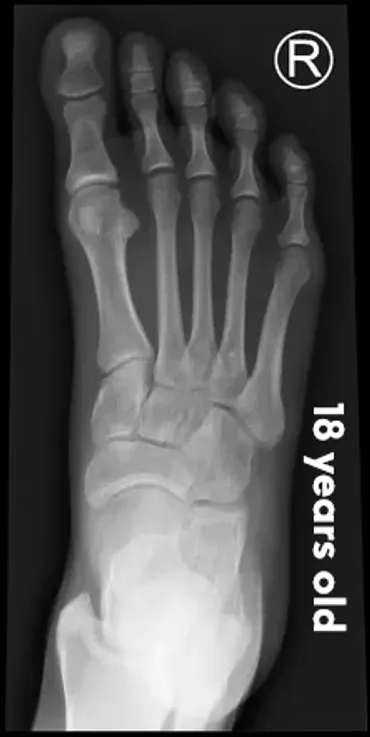

The pictures below will let you understand how babies' feet are developed. Here you can see how bones develop:

18 YearsDear parents, children’s feet are developing structures, and the absence of an arch is a typical stage of development. Detailed X-RAY pictures above let us understand that babies' foot bones are not connected till the teen years. Only at the age of 14 may we consider that the bones in the feet have reached their connections. At the age of 18, we have fully completed foot structure, where muscles and bones create the whole support system.